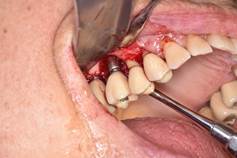

Clasificación de Peri-implantitis5

Avanzada: Profundidad de sondaje >8 mm, con sangrado y/o supuración en >2 sitios del implante, y pérdida ósea > 50% del largo del implante (Fig. 4).